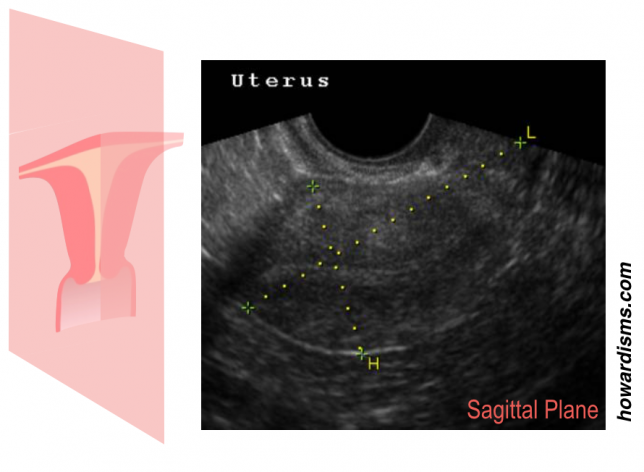

Hysterosalpingogram (HSG) is performed less commonly in modern gynecology than in the past, but it is still a valuable tool for some patients. A well performed HSG should be relatively painless and its results need to be correctly interpreted in context of what is already known about the patient. Here are four tips for performing an HSG.

2. Beware of the false positives.

One of the most common reasons for an HSG today is to check for tubal patency. Office-based saline-infusion sonography (SIS), especially when combined with a 3D reconstruction, is very effective for providing views of the uterus and cavity and this study (so-called virtual hysteroscopy) has essentially replaced HSG for exploring uterine malformations, Asherman Syndrome, etc.

3. Low pressure or high?

There are two somewhat different goals of HSG: to test the patency of the fallopian tubes and to visualize the contours of the cavity. Higher pressure of the contrast medium helps distend the walls of the uterus but is also more likely to cause tubal or cornual spasm, leading to a false positive result. So, a low pressure technique is more effective if the primary aim is to test the patency of the tubes, which is the most common objective of HSG. Inject the contrast medium at a slow and steady pressure and you shouldn’t need more than 2 or maybe 3 ml for the whole study. If the patient reports significant cramping, you are probably using a too much pressure (and that cramping may be associated with tubal spasm).